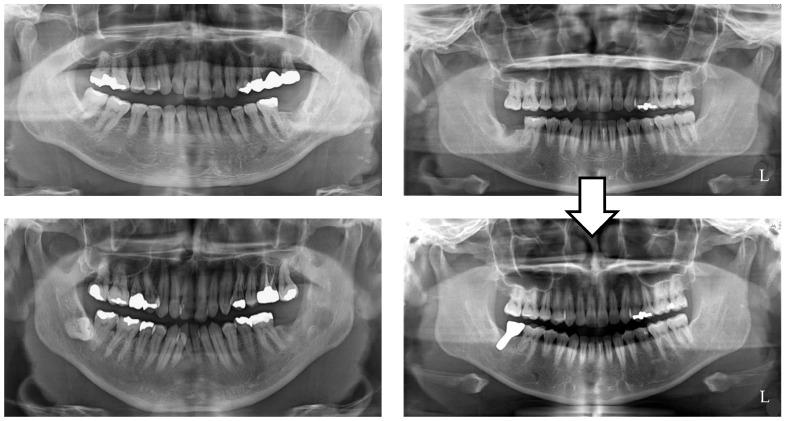

In this study, we aimed to investigate the association between a patient's selection of implant treatment for a missing mandibular second molar and the magnitude of occlusal force, masticatory ability, mandibular morphology, and age before treatment intervention.

We retrospectively assessed occlusal force, masticatory performance, and mandibular morphology in female patients who either selected or declined implant treatment for a missing unilateral mandibular second molar.

Thirty-three women (mean age of 56.1 ± 9.7 years) were divided into an implant treatment (IT) group and a no-treatment (NT) group. The IT group showed significantly higher occlusal force ( = 0.021 < 0.05), while masticatory performance and gonial angle demonstrated no significant difference.

The IT group had significantly higher occlusal force, and age had no significant effect on it. Notably, masticatory performance in the IT group increased significantly with age ( = 0.047 < 0.05).